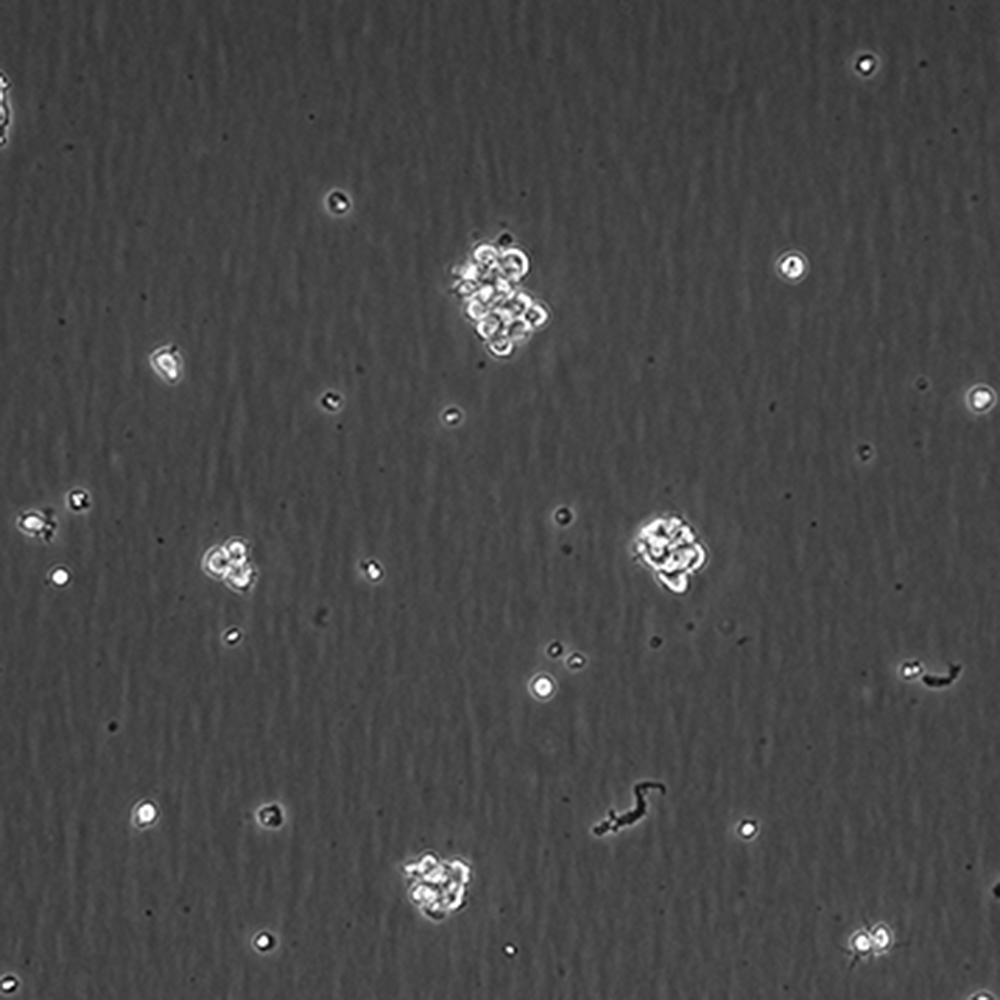

中文名稱 人間變性大細胞淋巴瘤細胞

組織來源 間變性大細胞淋巴瘤;胸腔積液轉移;女性

生長特性 懸浮

復蘇細胞步驟 將含有1mL細胞懸液的凍存管在37℃水浴中迅速搖晃解凍,加入4mL培養基混合均勻。在1000RPM條件下離心4分鐘,棄去上清液,補加1-2mL培養基后吹勻。然后將所有細胞懸液加入培養瓶中培養過夜(或將細胞懸液加入10cm皿中,加入約8ml培養基,培養過夜)。第二天換液并檢查細胞密度。